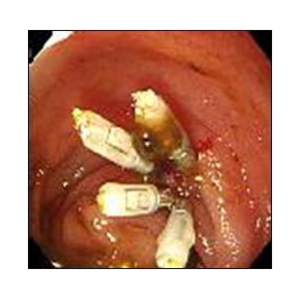

食道表在癌、早期胃癌の治療法として当科では積極的にESDを行っています。ESDとは内視鏡的に使用可能な高周波メスを使って、粘膜下層のレベルで病変を剥がし取る手技です。早期の小さな癌に対しては今までも内視鏡治療が行われてきましたが、ESDにより従来の内視鏡治療法(EMR)では切除困難であった大きな病変や、瘢痕を認める病変を一括切除できるようになりました。体を切開することなく組織も温存できるため、患者の身体的負担が少ない低侵襲医療のひとつです。

食道ESDは年間約15例、胃ESDは年間約40例ほど行っております。

《胃ESDの実際》